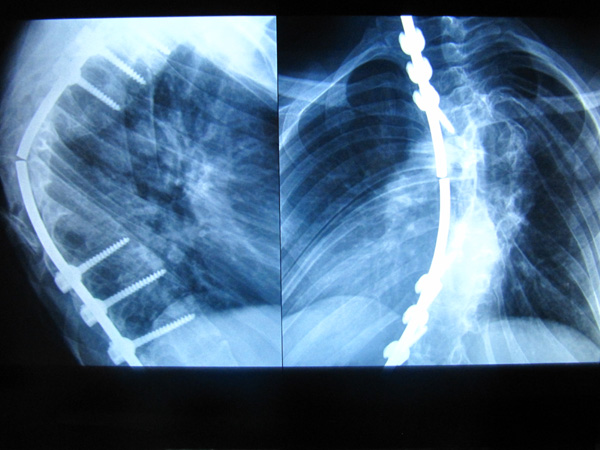

Диагноз: Сколиоз 4 степени.

Однако мама все - таки надеялась избежать операции. Но в 2007 году сколиоз прогрессировал настолько, что достиг уже 4-й степени и врачи настояли на операции (цель ее была – стабилизировать позвоночник). В киевском «Охматдете» мальчику были проведены в общей сложности три операции: в феврале и декабре 2008 г., в декабре 2010 г. После каждой из этих операций, через какое - то время стабилизирующая пластина ломалась, итог – новая операция. А для мамы Антона это новые долги, так как, каждый раз приходилось брать кредит на лечение.

Врачи объясняют эти поломки тем, что у Антона помимо сильнейшего искривления позвоночника – неврофиброматоз (онтогенетическое заболевание) и опухоль располагается как раз на позвоночнике. Также у этого совсем молодого человека есть сопутствующие заболевания, омрачающие его жизнь: диспластическая кардиопатия, диффузный зоб 2ст., ассоциированная мигрень. Каждое из этих заболеваний подрывает его и без того слабое здоровье. Но хуже всего то, что по прогнозам врачей, без операции Антону грозит паралич нижних конечностей. А этого допустить никак нельзя!